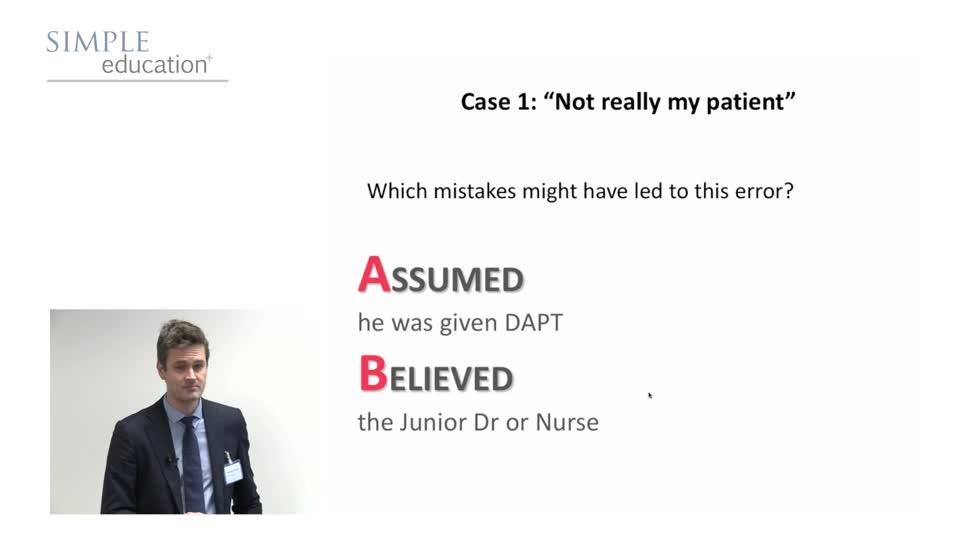

Recognise Post Angiography Problems Early and Treat Decisively - Ricardo Petraco